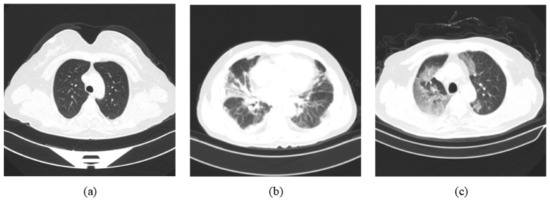

For the training and testing, we used two datasets, COVIDx CT-2 [11,12] and the integrated CT scan dataset [43]. The COVIDx CT-2 dataset has two diverse, large-scale datasets named COVIDx CT-2A and COVIDx CT-2B, and we chose COVIDx CT-2A. The patient cases collected in COVIDx CT-2A come from various organizations around the world, such as the China National Center for Bioinformation (CNCB), the National Institutes of Health Intramural Targeted Anti-COVID-19 (ITAC) Program, the Negin Radiology Medical Center, etc. The COVIDx CT-2A dataset contains 194,922 CT images (60,083 normal CT images, 40,291 images of patients with pneumonia, and 94,548 images of patients with COVID-19) from 3745 patients, with an image size of 512 × 512. In the integrated CT scan dataset, data are obtained from seven public datasets that contain 7593 COVID-19 images from 466 patients, 6893 normal images from 604 patients, and 2618 CAP images from 60 patients. In Figure 6, three categories of CT scan samples are illustrated, namely normal, COVID-19, and pneumonia. Among them, COVID-19 samples show a large number of GGO in the lungs. We divide the dataset into a training set, validation set, and test set in our experiments. For the COVIDx CT-2A dataset, we use 70% of the total samples for training, 10% of the total samples for validation, and 20% of the total samples for testing. For the integrated CT scan dataset, we use 60% of the total samples for training, 20% of the total samples for validation, and 20% of the total samples for testing. The specific distribution of the numbers is shown in Table 1.

Figure 6.

Dataset sample CT images [11,12]. (a) represents normal CT scan; (b) represents pneumonia CT scan; (c) represents COVID-19 CT scan.